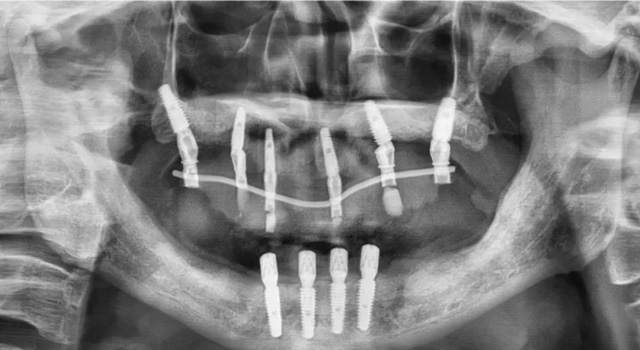

易华波医生为老人设计了上半口即刻种植方案,拔掉3颗原来的种植体,重新种植6颗新的种植体。“由于解剖结构的先天差异,我们上颌骨的骨密度比下颌骨要差一些,种植体的初期稳定性不如下颌骨,因此建议上颌种植6颗最为稳妥,特别是本身就有骨质疏松的人和高龄老人。”

听完方案,心情急迫的老人要求当天安排手术。通过即拔即种手术和即刻修复治疗,老人术后戴上了临时的固定牙冠,完成了上半口的种植和临时修复。

上半口重新种植6颗种植体

术后一周,易华波医生为老人完成了下半口种植治疗,让他如愿以偿用上了一口好牙。

下半口重新种植4颗种植体

戴牙后恢复全口24颗牙